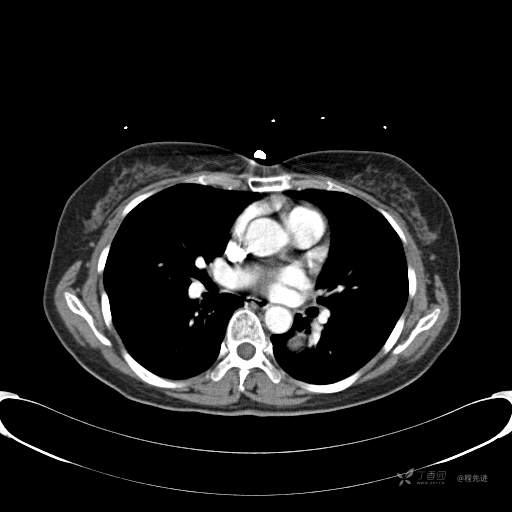

患者性别:女

患者年龄:57岁

简要病史:体检发现

CT增强

平扫CT值约40HU(未上传图像),增强后动脉期CT值约70HU,静脉期CT值约97HU。

肺硬化性血管瘤 (20)